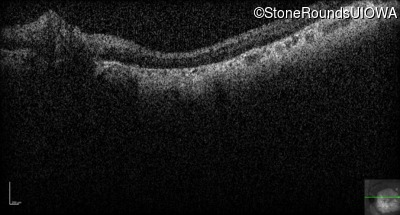

Optical Coherence Tomography - Right - 20/200 sc

Exemplar / OCT Stack

OCT Stack

Optical Coherence Tomography - Left - 20/200 sc